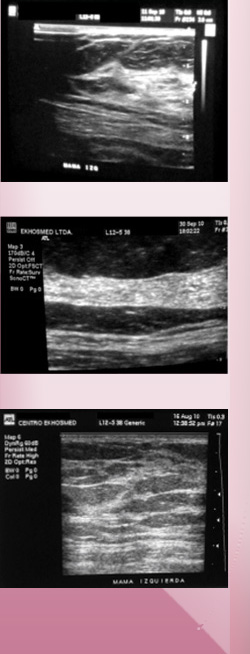

Es un examen ultrasonográfico de la mama, que utiliza ultrasonido. Es una técnica importante en el diagnóstico y manejo de las enfermedades de la mama, tanto benigna como maligna. En el informe mamográfico el radiólogo aconseja  la realización de una ecografía para profundizar en el diagnóstico.

La ecografía mamaria indicada en pacientes mayores de 35 años  como un examen complementario a mamografía, en mamas que debido a su gran densidad por gran cantidad de tejido glandular y fibroso, deben ser estudiadas con este examen complementario. También está indicada en mamografías que presentan nódulos, para ser caracterizados como sólidos o quistes.

Indicada en mujeres menores de 35 que no presenten factores de riesgo como antecedentes de familiar directo  de cáncer mamario. Únicamente en el caso de gestantes y mujeres muy jóvenes puede sustituir a la mamografía